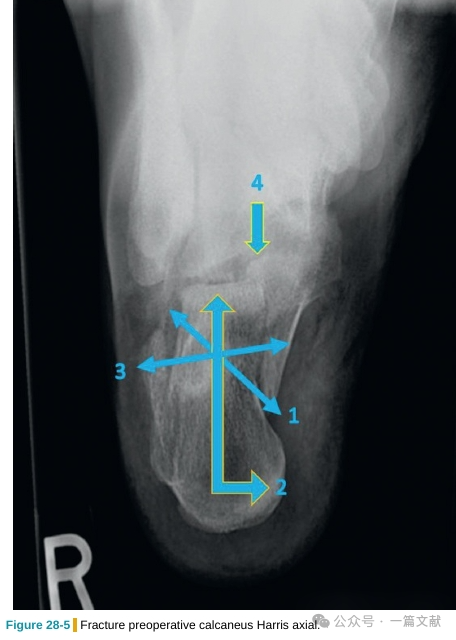

3.2跟骨轴位片:

常用于观察(1)主骨折线,(2)跟骨结节的外翻移位,(3)跟骨宽度;以及(4)后距关节面的损伤,如下图: